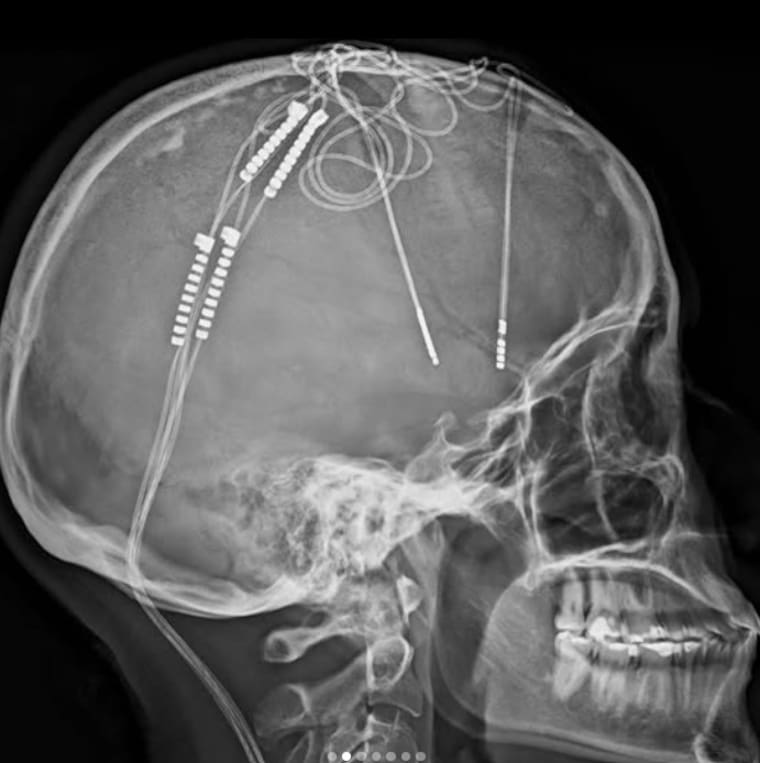

La cirugía, de aproximadamente seis horas, se realizó con la paciente despierta. Se implantaron electrodos en zonas específicas de su cerebro que controlan el estado de ánimo, los cuales se conectan a una batería colocada en el pecho, similar a un marcapasos.

El objetivo es modular la actividad cerebral alterada por la depresión mediante impulsos eléctricos. “Sentía que mi mente estaba siendo reprogramada”, dijo Lorena. “Superó toda ficción. Es increíble cómo la ciencia ha llegado tan lejos”.